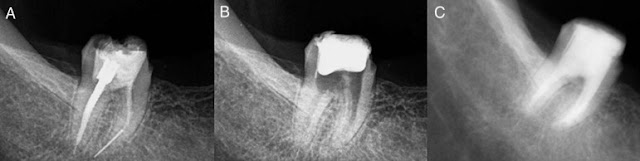

#6

Granted a pano doesn’t give all the information and neither does the article, but I see many teeth that look great.

#19-21 all look fine. #22 looks pretty good. And #30 may be fine also, mesial bone loss maybe??

Also pulling hem all and restoring with bar OD now eliminates all proprioceptive response and with nothing under the maxillary denture the patient is going to destroy the premaxilla. This contraindication (lower implant supported prosthesis vs max denture) can be found in many articles.

Either add 4 implants under maxillary denture with locators if patient insists doesn’t want teeth anymore or do fixed implant supported bridges on mandible where they are needed and maintain some natural teeth for proprioception.